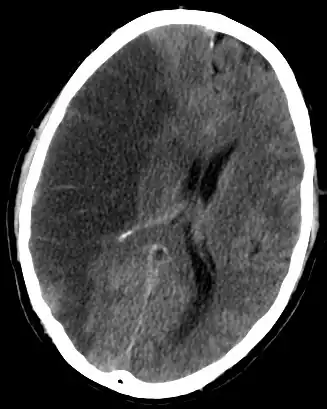

![]() Udar mózgu niedokrwienny – rozległy zawał mózgu w obszarze tętnicy środkowej mózgu z masywnym obrzękiem półkuli i towarzyszącym przemieszczeniem struktur środkowych (strzałka) |